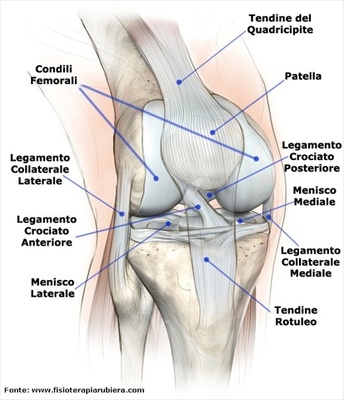

Il menisco un importante struttura fibrocartilaginea dell articolazione del ginocchio di forma semilunare. In ogni ginocchio esiste un menisco interno e uno esterno, collocati tra il femore e la tibia …

Vi abbiamo gi parlato in precedenza del dolore al ginocchio in un articolo specifico che puoi leggere qui. Il ginocchio un articolazione in cui entrano in gioco il femore, la tibia e la rotula.